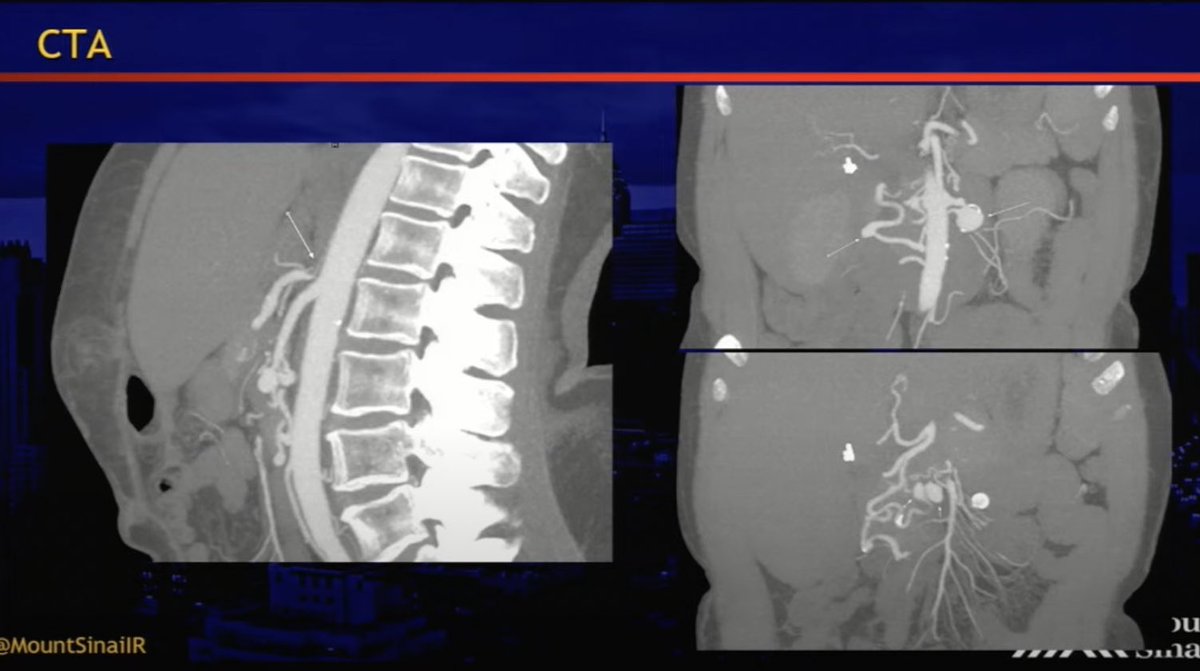

We authored an article for Medical Professionals CLT highlighting Genicular Artery Embolization (#GAE)—an innovative treatment for #kneepain caused by osteoarthritis. #irad @theobserver @wcnc @SIRspecialists